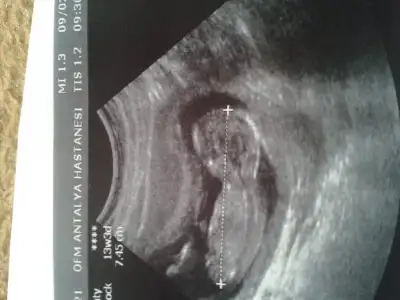

dr soylemeden siz gorun genital nub teorisi ( bebegin cinsiyeti)

12. haftayı geçince belli oluyormuş genelde ben de 15. haftada gidicem çek belki onda bellidir :KK48:

yook belli değil benim nub teorime göre kız :KK64: bide doktorum kıza benziyor dedi. ama kemik gelişimi erkek dedi kesin demiyorum dedi diğer geldiğinize kesinleştiririm dedi.